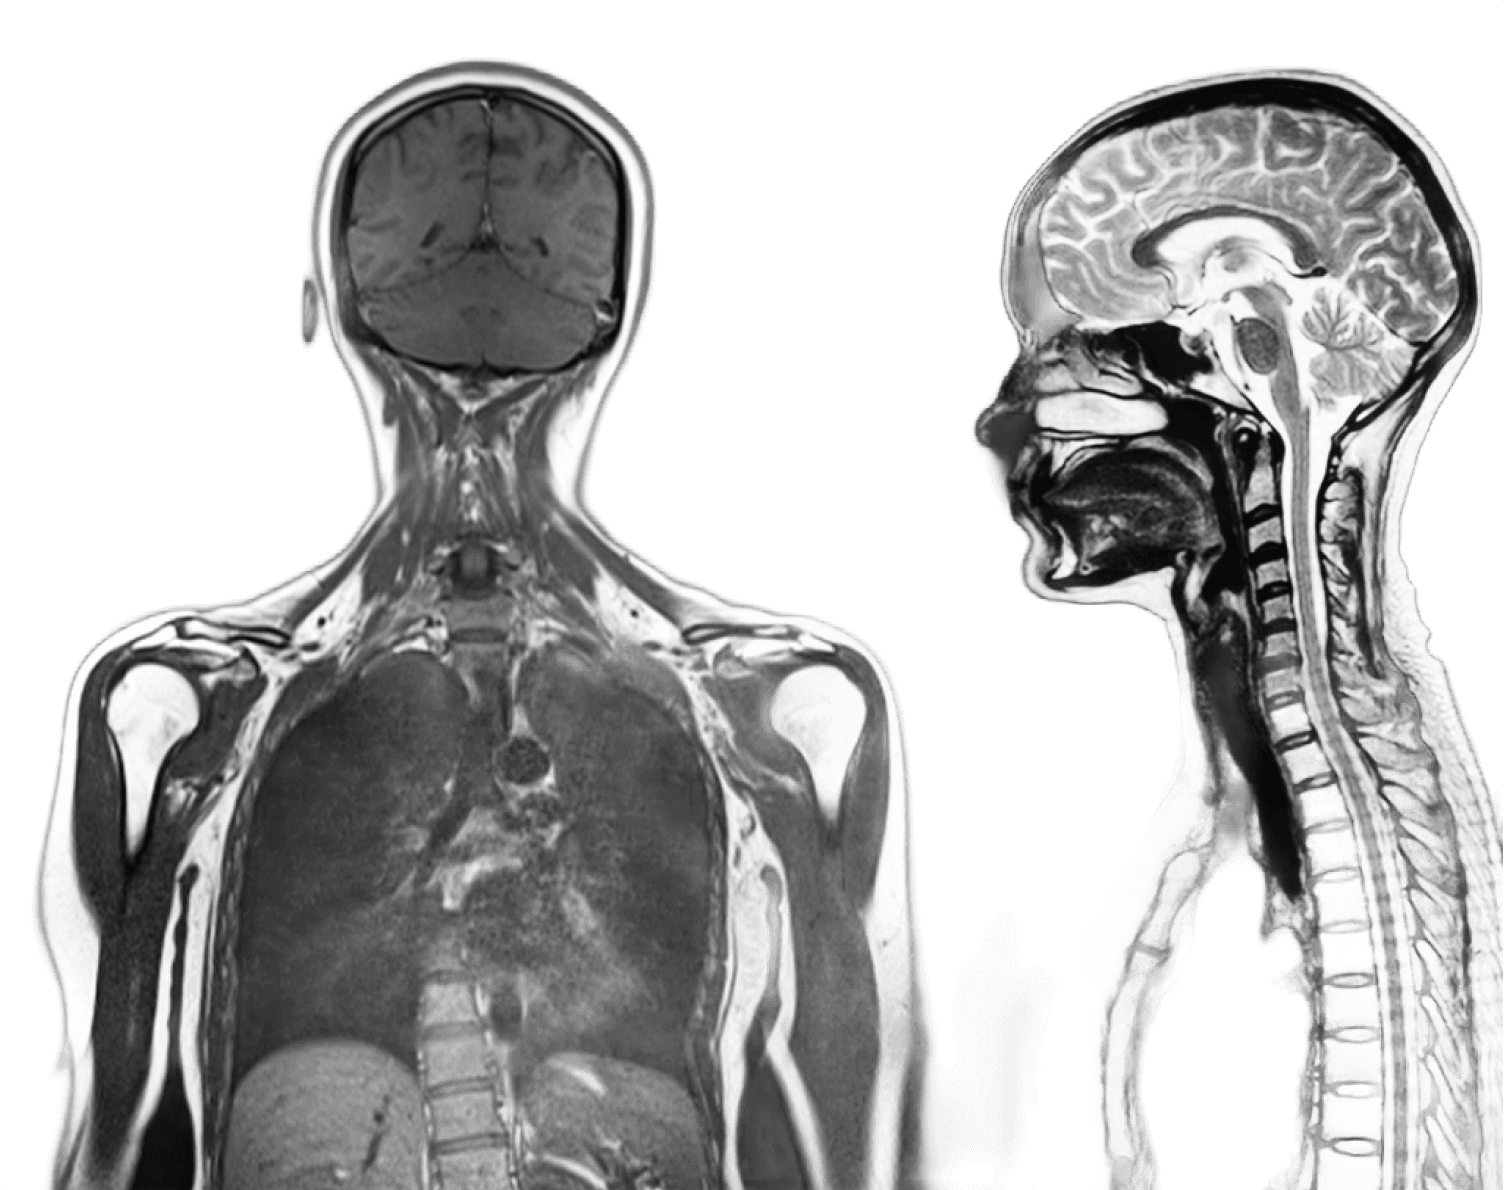

Thoughtful scan design behind every image

Each scan follows proprietary imaging sequences specifically for our screening approach, helping produce consistent views across organs, tissue, and structures throughout the body.